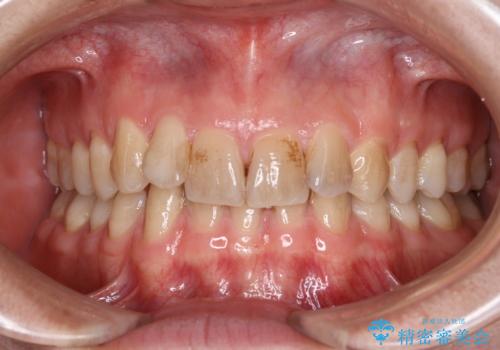

- 歯の色が気になり、ホワイトニングを考えているとのことで来院されました。

ホワイトニングは、歯の表面の汚れや着色を全て除去してからでないと効果が出にくいため、まずはクリーニングのご案内をしました。

エアフロー60分コースを行いました。

着色の除去後に、ご自身の本来の歯の色をご確認していただいたところ、この状態で満足とのことでした。